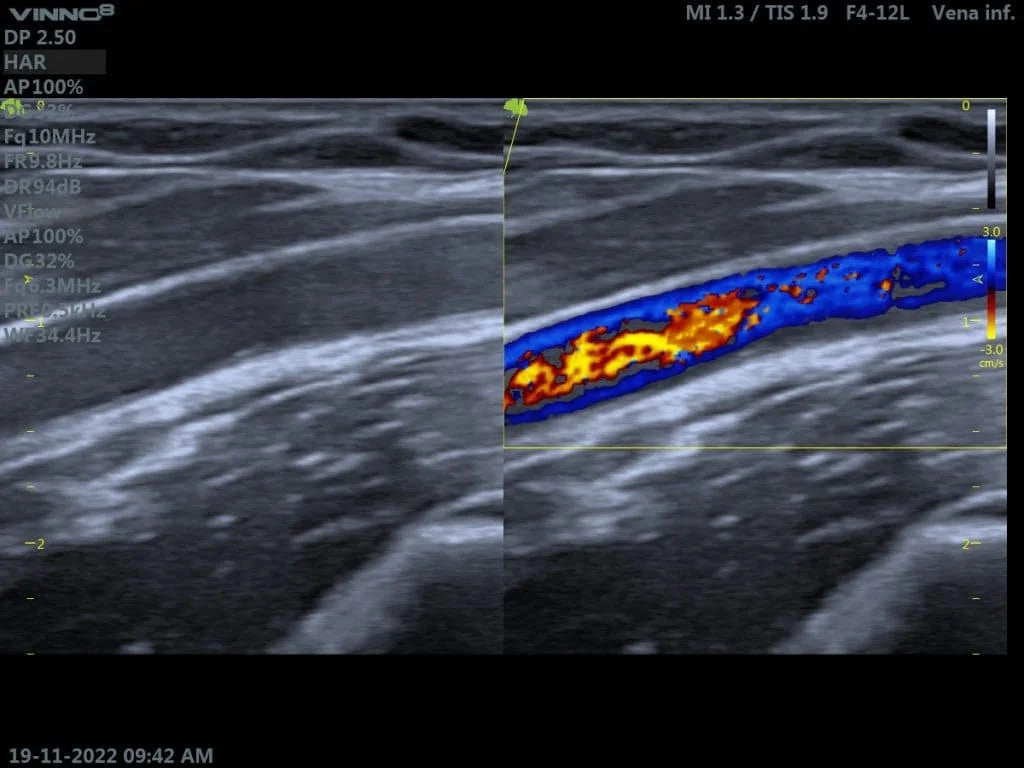

- En la imagen proporcionada, se observa un estudio de una vena (indicado en la parte superior derecha de la pantalla con el término “vena inf.”) en el cual se ha utilizado un Doppler en color para analizar el flujo sanguíneo. Los colores rojo y azul que aparecen en la imagen representan la dirección y la velocidad del flujo sanguíneo en el vaso estudiado:

- Colores rojos y amarillos: Indican el flujo sanguíneo hacia el transductor.

- Colores azules: Indican el flujo alejándose del transductor.

- La imagen Doppler fue capturada con los siguientes parámetros que pueden observarse a la izquierda del panel:

- Frecuencia del transductor: 10 MHz, una frecuencia alta ideal para estudios vasculares superficiales como el de la imagen.

- Doppler PRF: 0.37 Hz, una baja frecuencia de repetición de pulsos para detectar flujos lentos.

- Profundidad: La configuración parece estar ajustada a una profundidad que permite visualizar la vena de interés en el plano adecuado.